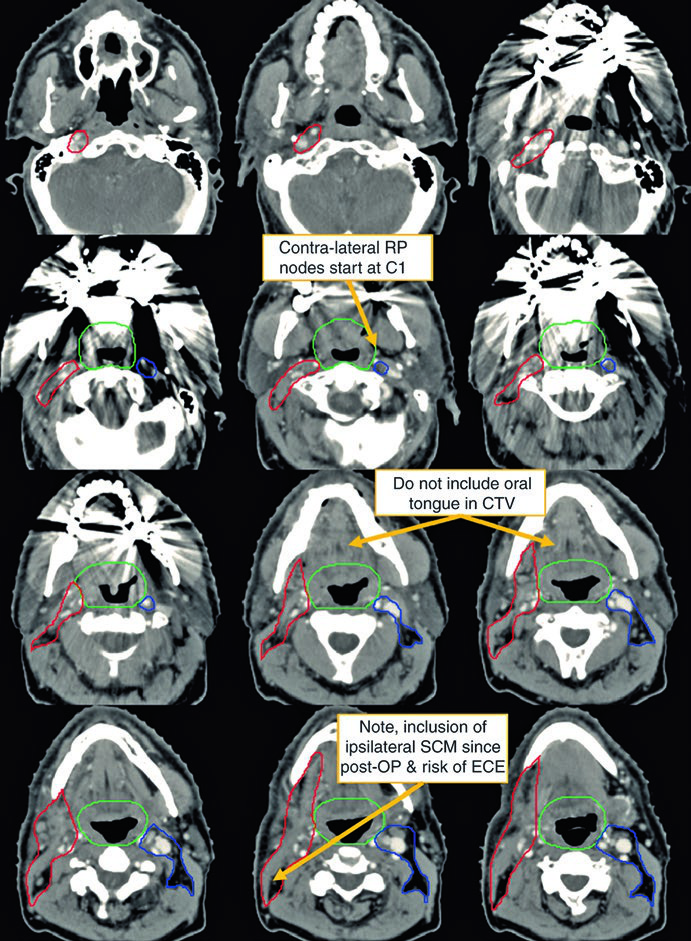

O segundo caso demonstra um cenário mais agressivo: homem de 50 anos com TxN2c, biópsia aberta de linfonodo à esquerda demonstrando extensão extranodal, HPV ISH e p16 negativos. Recebeu quimiorradioterapia definitiva.

Neste caso, o CTV70Gy (vermelho) engloba a doença macroscópica bilateral; o CTV60Gy (verde) cobre as mucosas faríngeas em risco; e o CTV54Gy (azul) inclui todo o pescoço bilateral profilaticamente. A negatividade para HPV justifica a cobertura abrangente de toda a faringe, pois sem a orientação viral para um subsítio específico, o risco é distribuído ao longo de todo o eixo mucoso.

A presença de ECE neste caso reforça a indicação de quimioterapia concomitante. A dose de 70 Gy na doença macroscópica e 54–60 Gy nas mucosas em risco segue o escalonamento padrão. Compare essa abordagem com as estratégias específicas para câncer de laringe, onde o foco é preservar a função laríngea.